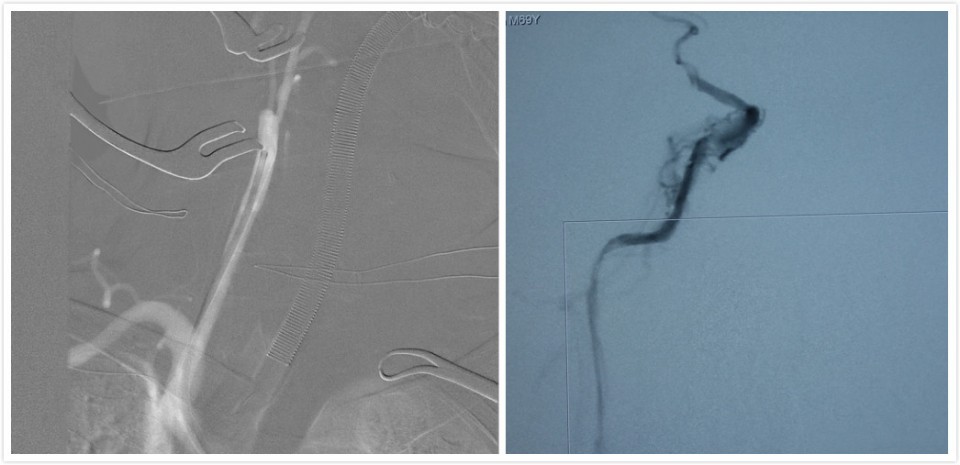

患者男性71岁,因“头晕伴左侧肢体无力3月”入院,就诊于我院神经外科。头颅CT提示:1.多发腔隙性脑梗塞2.右侧基底节及外囊区梗塞。行全脑血管造影(DSA)提示右侧颈内动脉起始段闭塞,颅内段血管显影不佳。患者高龄,既往有高血压、糖尿病、高脂血症、心脏病等、病情复杂。如不及时予以治疗,将可能发展为大面积脑梗塞,危及生命。王晓健副主任医师团队详细分析患者资料后,结合相关文献并借鉴国内先进单位成熟技术,决定对患者实施闭塞颈动脉开通术(CEA+颅内外支架植入的复合手术)。切开颈内动脉,剥除斑块,同时在颈内动脉狭窄段放入支架。术后造影显示闭塞动脉开通满意,血管通畅,患者恢复良好,3—4天后即可在辅助下行走,一周后就已顺利出院。

术中DSA